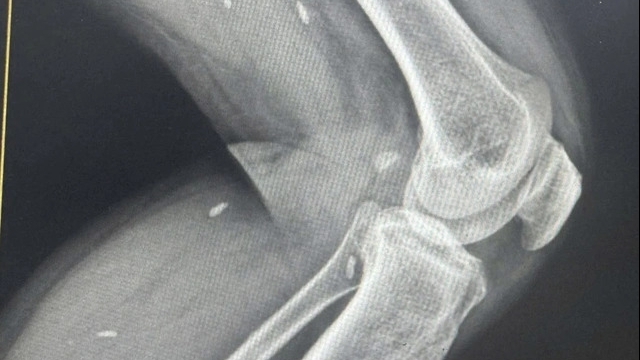

| Cán bộ y tế kiểm tra sức khỏe cho người cao tuổi |

Người cao tuổi được siêu âm ổ bụng (gan, thận, túi mật, tụy, lách, bàng quang, tử cung, buồng trứng ở nữ giới, tuyến tiền liệt ở nam); Đo chỉ số cơ thể (mỡ nội tạng, mỡ cơ thể, tỷ lệ cơ xương); Kiểm tra chỉ số huyết áp.